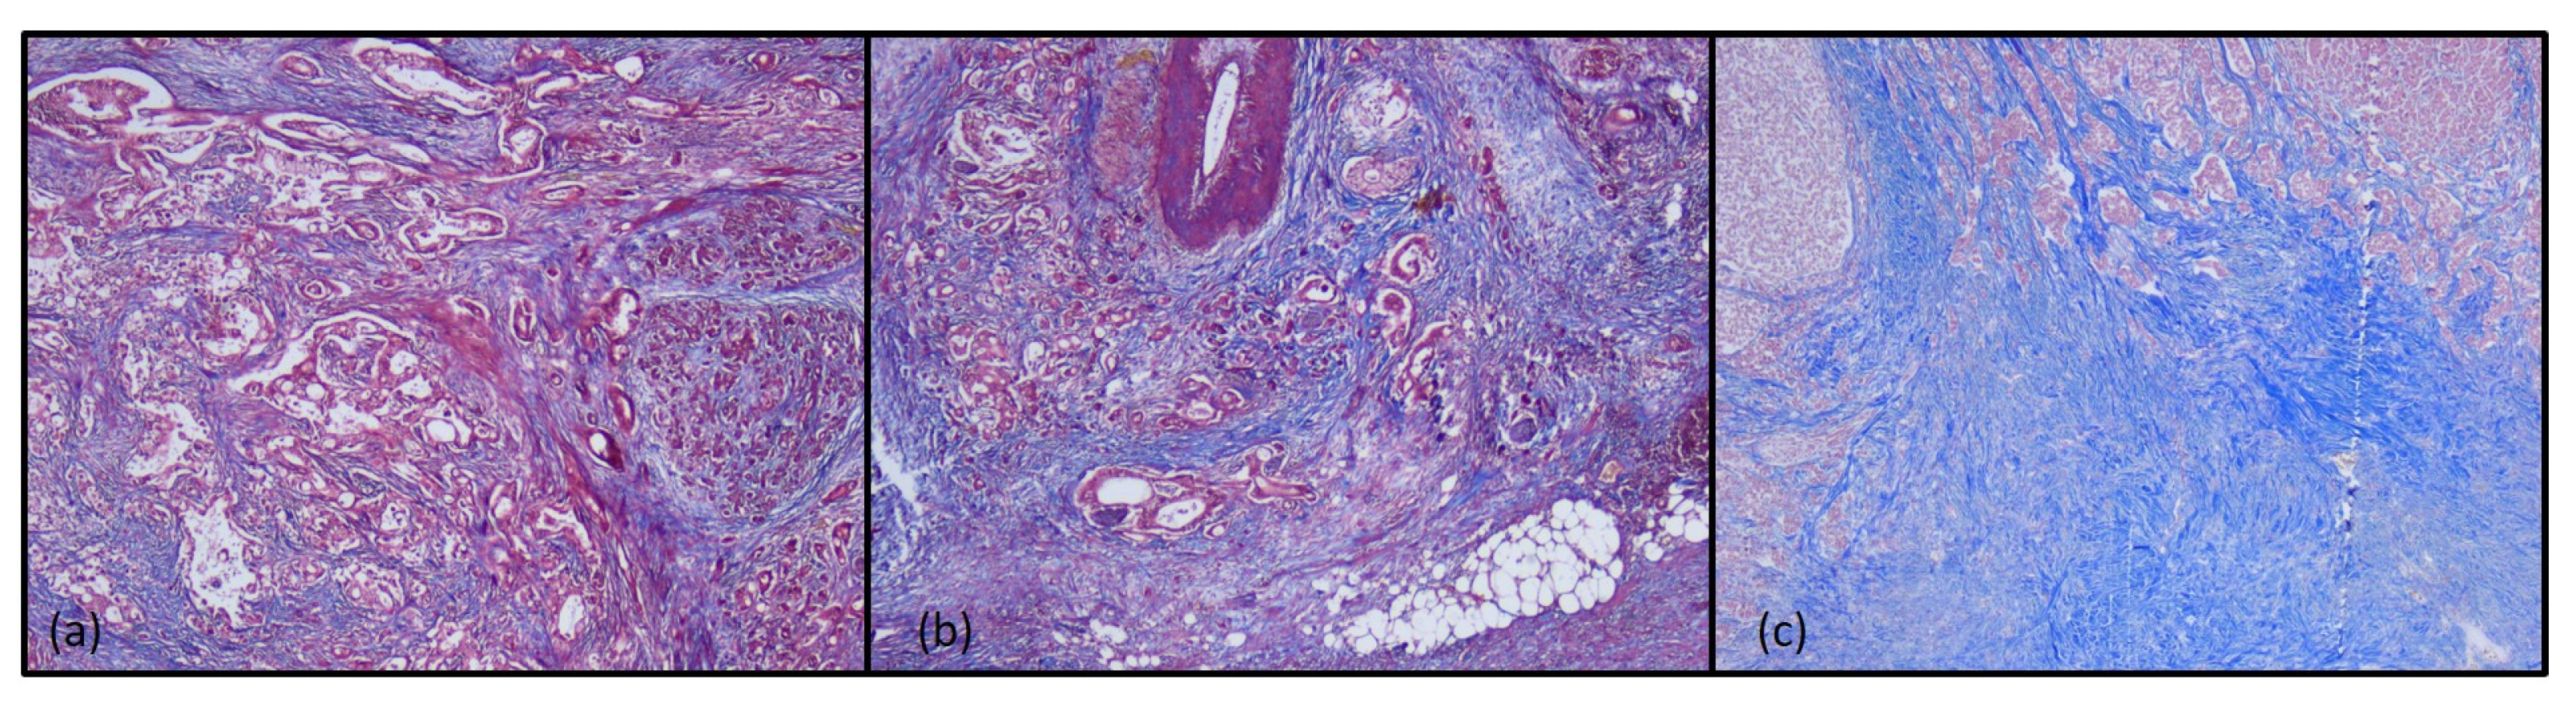

3.1. Histopathological Findings